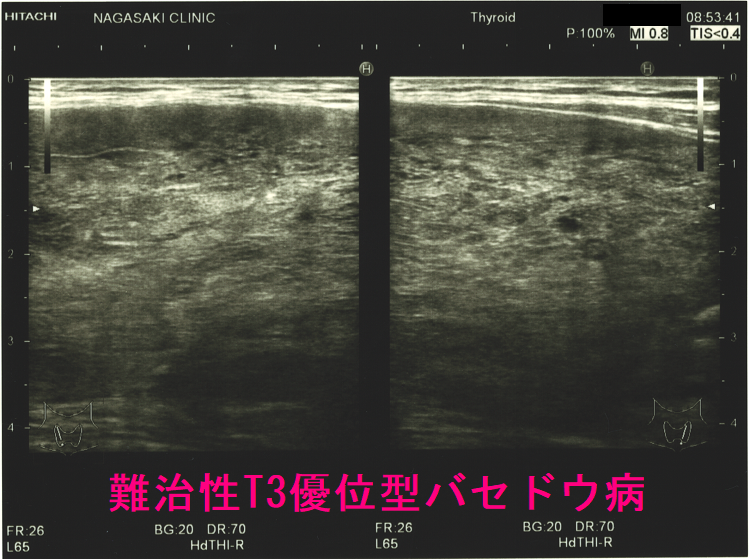

T3優位型バセドウ病の超音波(エコー)所見

ケース② 巨大甲状腺腫・甲状腺内部血流増大

ケース③ 異常に太い下甲状腺動脈